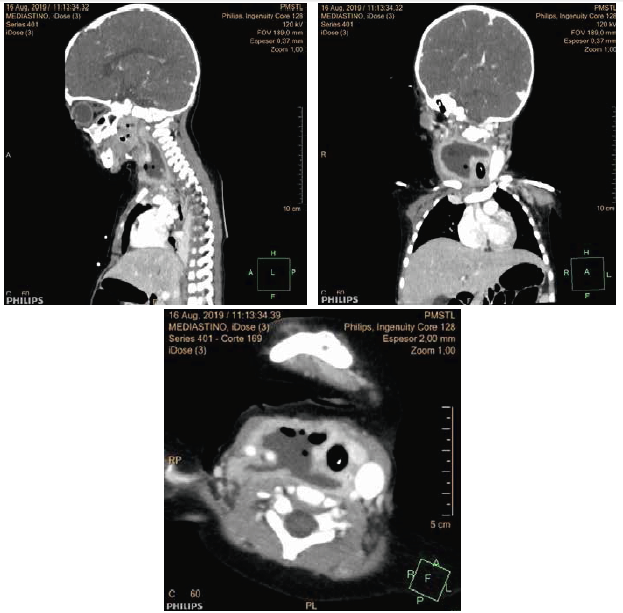

A nivel de cuello derecho predominantemente suprahioideo con extensión infrahioideo en compartimiento carotídeo y retrofaríngeo ipsilateral existe la presencia de colección abscedada con cápsula semigruesa definida captante de contraste, de 42x20x48 mm de tamaño en sus diámetros longitudinal, anteroposterior y transversal respectivamente, con contenido líquido con burbujas de aire en su interior. Además, presenta sutil infiltración de la grasa mediastínica superior y datos de mediastinitis. Presentó focos múltiples de condensación en relación a neumonía multifocal, probablemente por broncoaspiración.